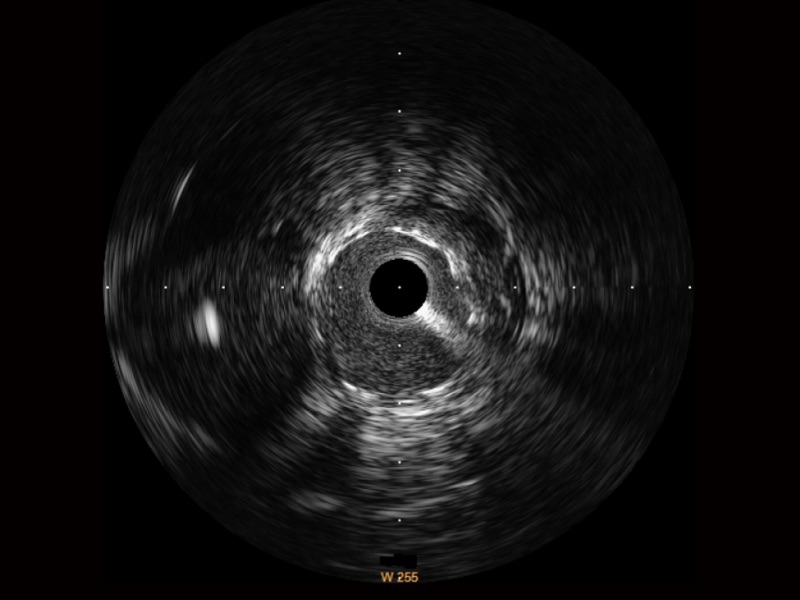

传统IVUS图像

对比传统IVUS导管成像,新葡的京集团8814检测站宽频IVUS图像的近场支架梁显影更细腻,远场中膜外血管仍清晰可辨,兼顾远中近,兼顾分辨力与穿透深度